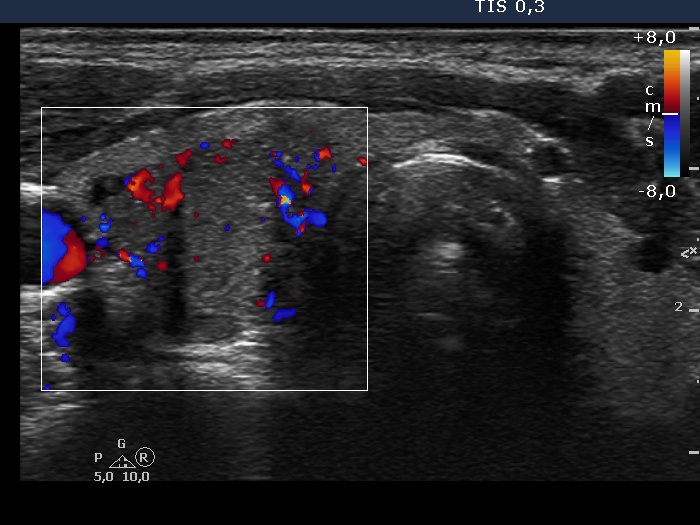

Ultrasonography. The thyroid was echonormal. There was a hypoechogenic nodule presenting irregular lobulated margin and intranodular hyperechogenic figures including microcalcifications. The nodule had an irregularly increased intranodular vascularization. A small, moderately hypoechogenic inhomogeneous lesion was found in the left lobe.